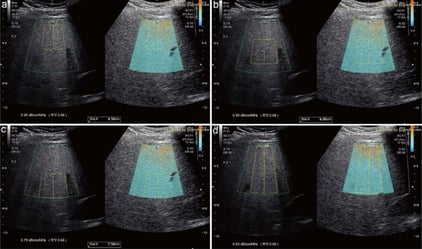

QAI: cuantificación objetiva de la esteatosis

El Coeficiente de Atenuación Ultrasónica (QAI) permite cuantificar el contenido graso hepático.

¿Qué mide?

La atenuación del haz ultrasónico al atravesar el hígado.

La grasa incrementa dicha atenuación.

Resultados

- Expresados en dB/cm/MHz.

- Valores crecientes se correlacionan con esteatosis leve, moderada o severa.

Utilidad clínica

- Detección precoz de esteatosis antes de cambios morfológicos evidentes.

- Evaluación en síndrome metabólico.

- Seguimiento de intervenciones terapéuticas (dieta, fármacos, descenso ponderal).